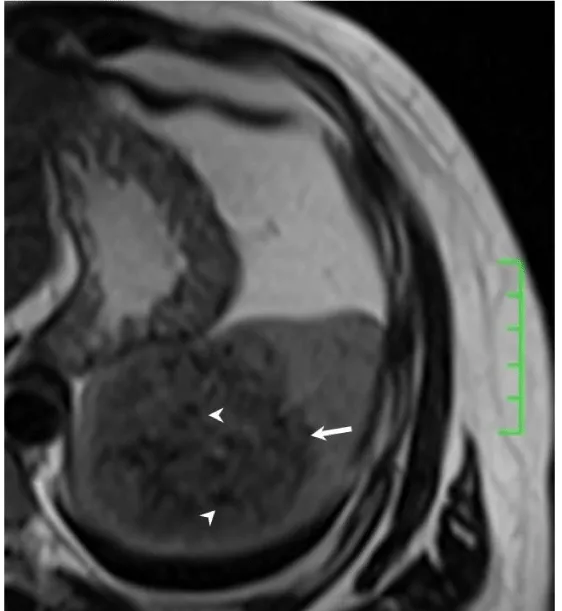

Solitary well-circumscribed masses were detected in all the five patients by ultrasound. One mass was of hypoecho, while the remaining masses were of hyperecho with posterior enhancement (Figure 1A). The maximum diameter ranged from 3.0 cm to 9.0 cm. At CT scanning, two masses appeared as hypodense (Figure 1B) and one was isodense (Figure 2A) to the normal spleenic parenchyma. In the two patients who received MR imaging, masses were isointensity at T1 weighted images (Figure 3A) and hypointensity with scattered sign void spots at T2 weighted images (Figure 3B). After intravenous injection of the contrast materials, all the five masses presented circle enhancement at arterial phase (Figure 3C and Figure 4A), while peripheral enhanced node was noted in one mass (Figure 2B). The circle enhancement persisted and radical line enhancement were observed at portal vein phase in 3 cases (Figure 1C) and progressive filling in was seen in two cases (Figure 2C). At delay phase of MR imaging, one lesion showed obvious enhancement with stellate low signal scar in the center comparing with surrounding splenic parenchyma (Figure 3D), while the other demonstrated central and circle enhancement to form a spoke-like appearance (Figure 4B). At delay enhanced CT scanning, two masses were isoattenuation to the surrounding splenic parenchyma (Figure 2D) and one lesion kept as hypoattenuation but with radial enhanced lines and enhanced circle to form a spoke-like appearance.

At pathological examination, all the masses were well demarcated on gross cut surface. A central stellate scar with peripheral interspersed dark brown nodules and the whitish intervening fibrous bands was noted to form spoke-like appearance (Figure 3E), which was well correlated with CT and MR imaging findings at enhancement. Microscopically, these angiomatoid nodules were surrounded by dense concentric collagen fibrous stroma and dispersed stromal cells with oval-to-spindle nuclei and scanty cytoplasm (Figure 3F). The abunden fibrous stroma may result in hypointensity at T2 weighted MR images. Hemosiderin was noted in the angiomatoid nodules (Figure 3G), which might contributed to signal void at T2 weighted MR images.

It usually affects middle-aged adults [6] and it is commonly found incidentally on radiographic imaging, or during operation for an unrelated condition. In present series, the patients are middle-aged adults without any related symptoms and the lesions were detected incidentally at routine ultrasound of health examinations. On ultrasound, manifestations of SANTs are vary widely from heterogeneous echo-texture with hyperechogenic, hypoechogenic, or isoechogenic appearing lesions, which are unspecific [7,8]. CT and MRI can show some characteristic features of SANTs, which include a solitary well demarcated mass with early peripheral enhancemant with radiating lines and progressive enhancement at the delay phase, and hypointens at T2 weighted MR images [2,3,5,9-13]. These features reflect the underlying pathological changes of scattered angiomatoid nodules separated and surrounded by sclerotic fibrotic stroma [10]. In present series, we also observed these characteristic features with well correlation to pathological findings. Circle and spoke-like enhancement can be contributed to fibrotic stroma surrounding and separating the angiomatoid nodules. The sclerotic fibrotic stroma may also result in isodense on CT, isointensity on T1 weighted images and hypointensity on T2 weighted images of MR imaging. The signal void spots at T2 weighted MR images have not been described at other literatures and may be contributed to hemosiderin deposition due to magnetic susceptibilty artifact.